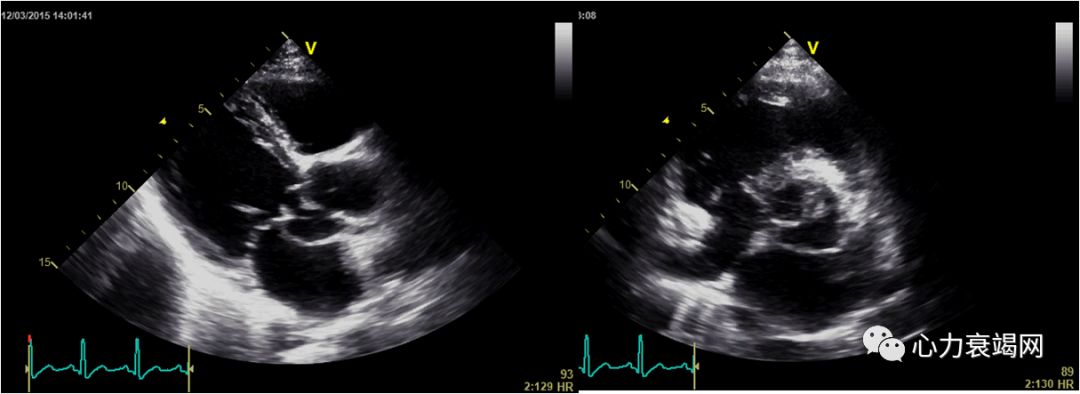

女性28 岁,因发热、皮疹7 个月余,反复胸闷、胸痛3个月余。诊断PAN

超声心动图:双平面法LVEF48%,左心室心尖部、后壁中下部运动减弱,心尖部变薄)。左心室增大。轻度二尖瓣关闭不全,左冠状动脉7.5mm, 右冠状动脉8mm

三支病变

激素+CTX

抗血小板+降压+他汀

抗心衰

症状有所好转

冠状动脉炎(60%)

少数为间质性心肌炎和心包炎

充血性心力衰竭常见。